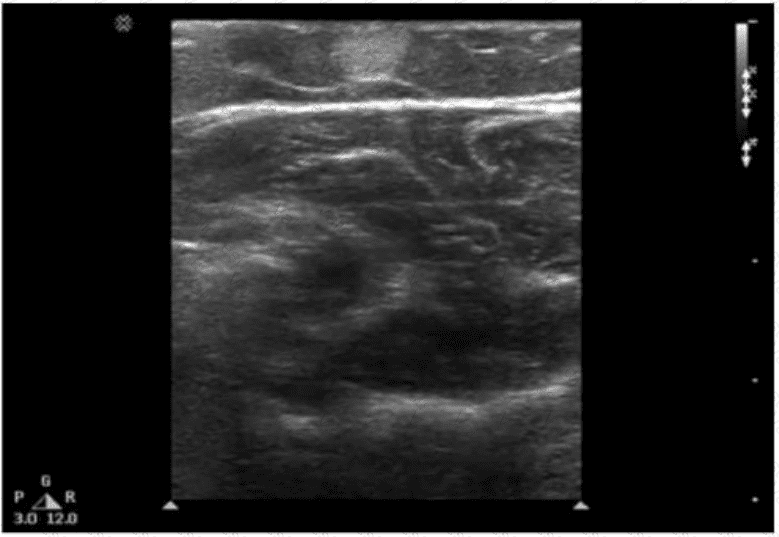

Which condition is most likely depicted in this image?